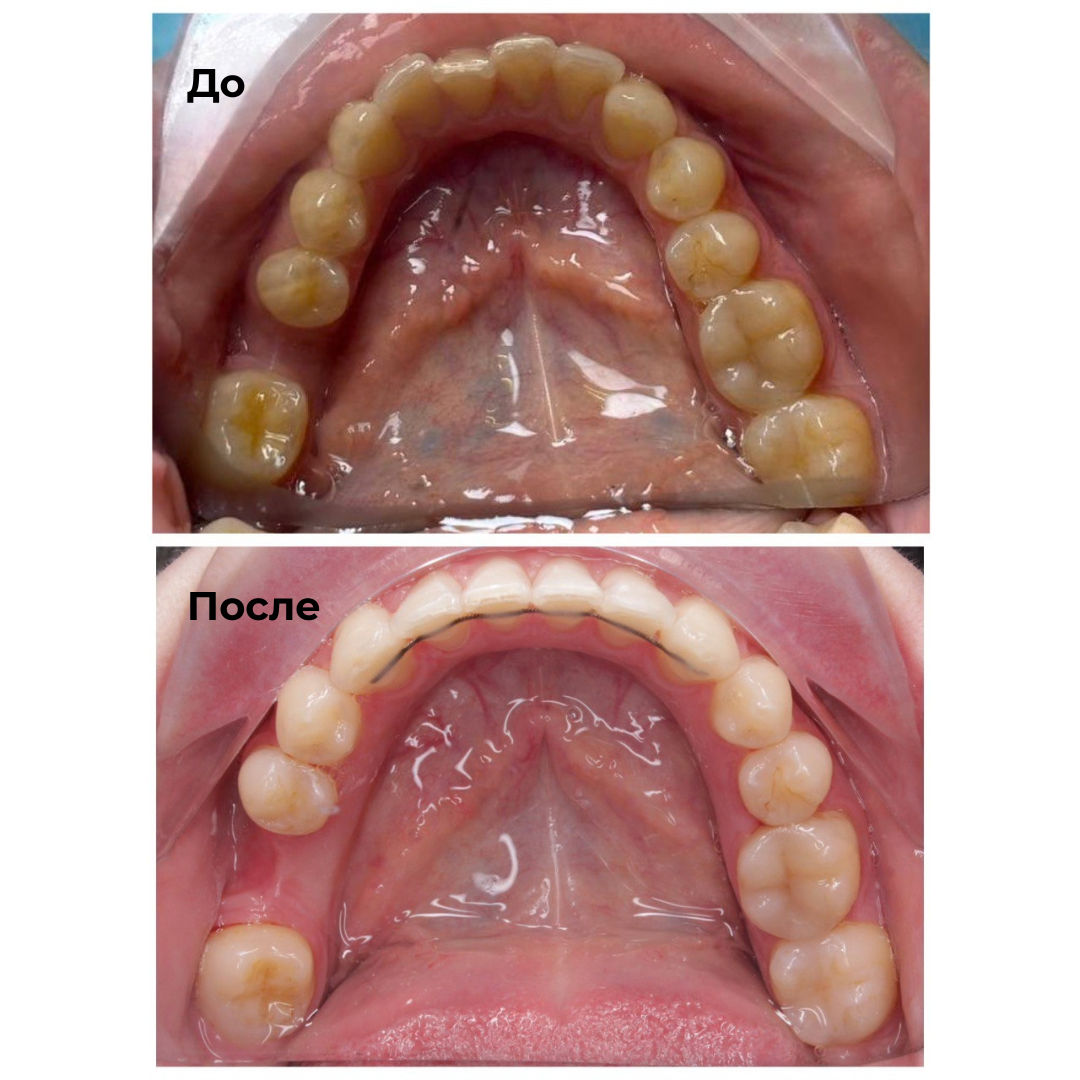

Такие результаты получают наши пациенты после лечения

Каждый случай - индивидуальный, но результат один: ровные зубы

Запишитесь на консультацию — подберём оптимальный план лечения под ваш случай.